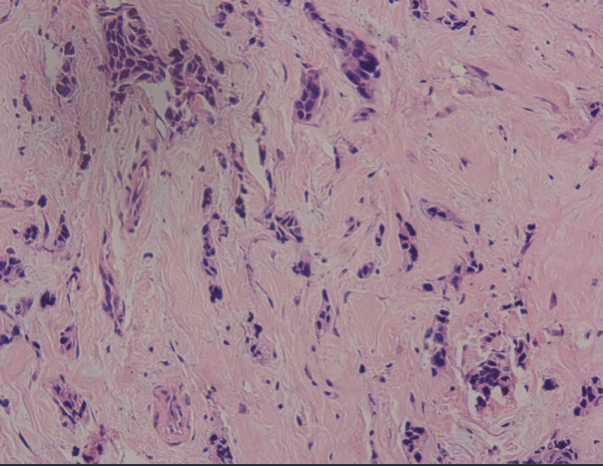

2022-2-22病理:(右乳肿物)乳腺浸润性癌。

2022-3-4免疫组化:ER*(+90%,中-强),PR*(-),HER2*(3+),Ki-67#(+约50%)

HE染色